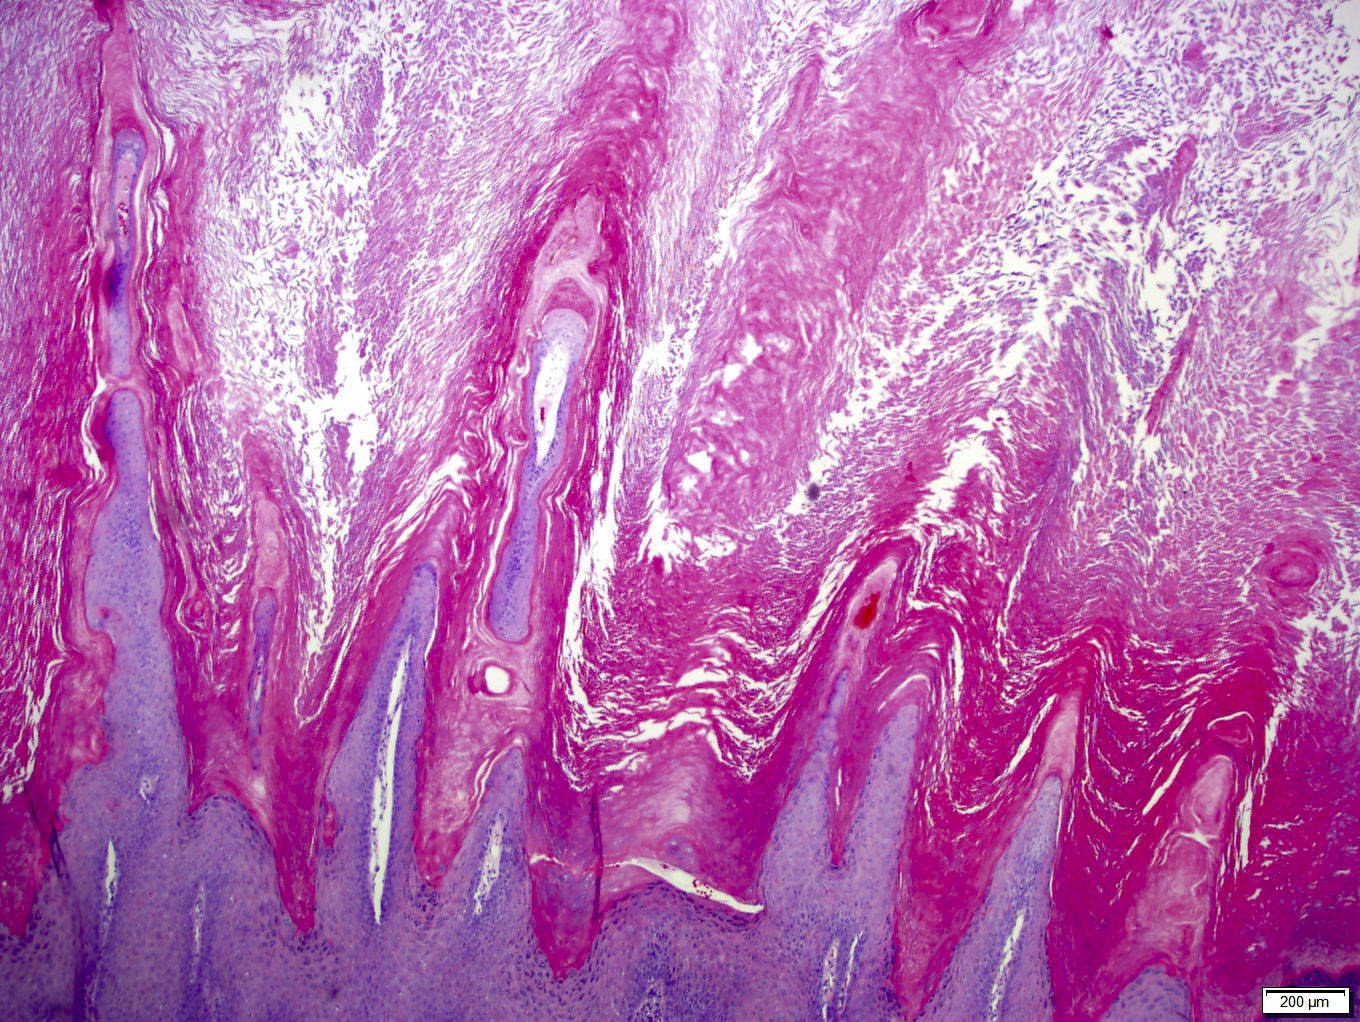

Microscopic (histologic) description

- Palmar / plantar warts (verruca palmaris and verruca plantaris) (Arch Pathol Lab Med 2018;142:700):

- Similar to verruca vulgaris (clinical distinction based on location)

- Endophytic growth - greater proportion of the lesion lies beneath the plane of the epidermis

Microscopic (histologic) images

Contributed by Heba Ahmed Abdelkader, M.D., Hillary Rose Elwood, M.D., AFIP,

@MirunaPopescu13 on Twitter and @shilpa_rakesh_path on Instagram